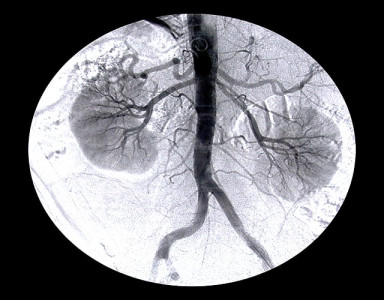

SIUT performs first renal transplant in Sukkur

Australian expert calls for adoption of ethical transplant practices in Pakistan

SIUT organises workshop to discuss renal transplantation

SIUT carries out two successful liver transplants

Patients are now out of intensive care unit and making good progress, say sources